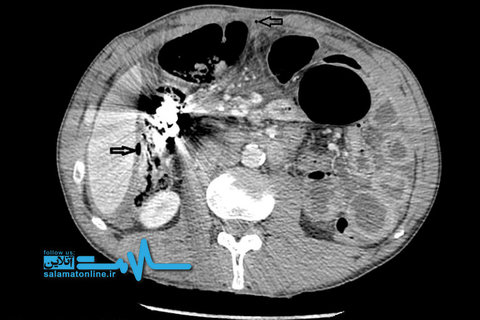

داکتران از شکم مردی ۵۲ ساله که بارها اشیاء تیز و غیرمعمول خورده بود، انبوهی از قطعات فلزی را خارج کردند.

مردی که سالها به بیماری روانی سایکوز مبتلاست و به همین دلیل عادت به بلعیدن اشیائی فلزی و غیر معمول دارد، پس از ۵ بار عمل جراحی بار دیگر در بیمارستان بستری شد و جراحان از شکمش تودهای فلز و اشیاء دیگر خارج کردند.

به نقل از بیامجیکیس ریپورت، قطعاتی که وی خورده بود در طول زمان به یکدیگر متصل شده و تودهای به نام bezoar تشکیل داده بودند که میتواند در هر جایی از دستگاه گوارش، از جمله معده شکل بگیرد.

این بیمار روانپریش که نامی از او برده نشده، طی ۵ سال گذشته و در پی درد شدید و بالاآوردن خون ناشی از تجمع قطعات مذکور، ۵ بار دیگر تحت عمل جراحی قرار گرفته بود و هر بار چیزهایی چون چاقو، ناخن، پیچ، پیچگوشتی، قاشق، ریگ و سنگریزه، سیم آهنی، و سکه از شکمش بیرون آورده شده بود.